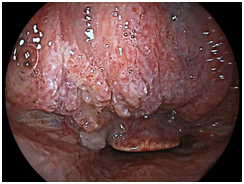

We detected 11 cases of superficial squamous cell carcinoma of the base of the tongue between April 2012 and March 2016. All the patients were complicated with current (n=3) or previous (n=8) esophageal squamous cell carcinoma. The patient characteristics are shown in Table 1. The mean age of the patients was 63.7years (range, 49-73years), and all patients were male. Four cases were diagnosed using trans-nasal endoscopy with the FICE system, seven cases were diagnosed using trans-nasal endoscopy with the LASERIO system. The average time to complete a thorough examination for one patient was approximately from 1 to 2minutes, regardless of the presence of abnormal findings. Biopsy specimen were obtained in all patients, and diagnosed as squamous cell carcinoma pathologically. Table 2 shows the treatment results. Five lesions were flat type (Figure 4A), four were elevated (Figure 4B), and two were depressed (Figure 4C). Regarding the tumor size, eight were T1, three were T2. No lymph node metastasis was detected in any case. Six cases were treated by endoscopic laryngo-pharygeal surgery,15 and 3 cases were treated by chemo-radiotherapy. One case was followed because of esophageal cancer. One case was treated by trans-oral robotic surgery at another hospital. For the seven resected specimens, the median tumor thickness was 800μm (range, 250-3000μm), and the median tumor diameter was 11mm (range, 10-25mm). Histologically, two of these lesions were squamous cell carcinoma in situ, five showed microinvasion of the subepithelial tissue. During a median follow-up period of 26months (range,11-56months), 1 patient, which patient’s tumor thickness was 3000μm, developed lymph node metastasis, which was treated by neck lymphadenectomy and chemo-radiotherapy. Three of the 11 patients cases were died of another disease, and 8 were alive as drafting this manuscript.

Figure 4B Elevated type.

Macroscopic types of superficial squamous cell carcinoma of the base of the tongue.